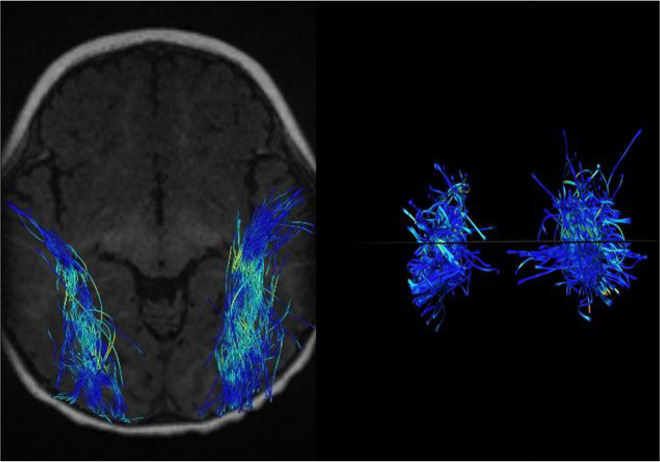

Methods: Twenty-two children including 11 subjects with SNHL aged 1-4 years and 11 healthy children were examined as controls. Then, DTI-derived parameters, such as fractional anisotropy (FA), mean diffusivity (MD), axial diffusivity (AxD), and radial diffusivity (RD), and volume of fiber tracts were extracted from the inferior longitudinal fasciculus, acoustic radiation, and uncinate fasciculus.

Results: The results showed an increase in MD, RD, and AxD as well as a decrease in FA, volume, and diameter of auditory-pathway-related fiber tracts. Interestingly, there was an increase in the FA of acoustic radiation.

Conclusion: White matter connections in the auditory canal decrease and AR integrity increases due to compensatory effects. These probably reflect atrophy or degradation as well as compensatory cross-modal reorganization in the absence of auditory input and the use of sign language.